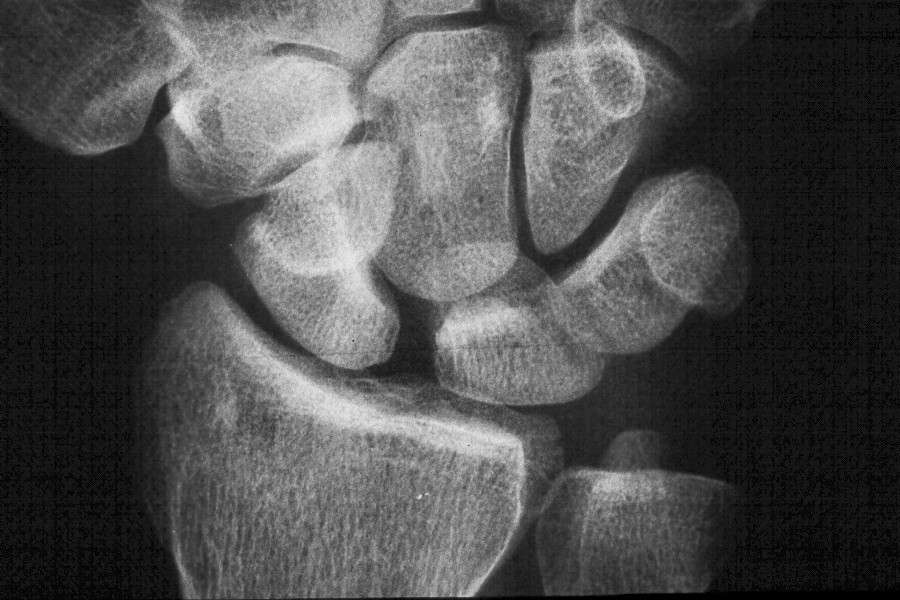

Scapholunate diastasis.

Click for larger image

Preop